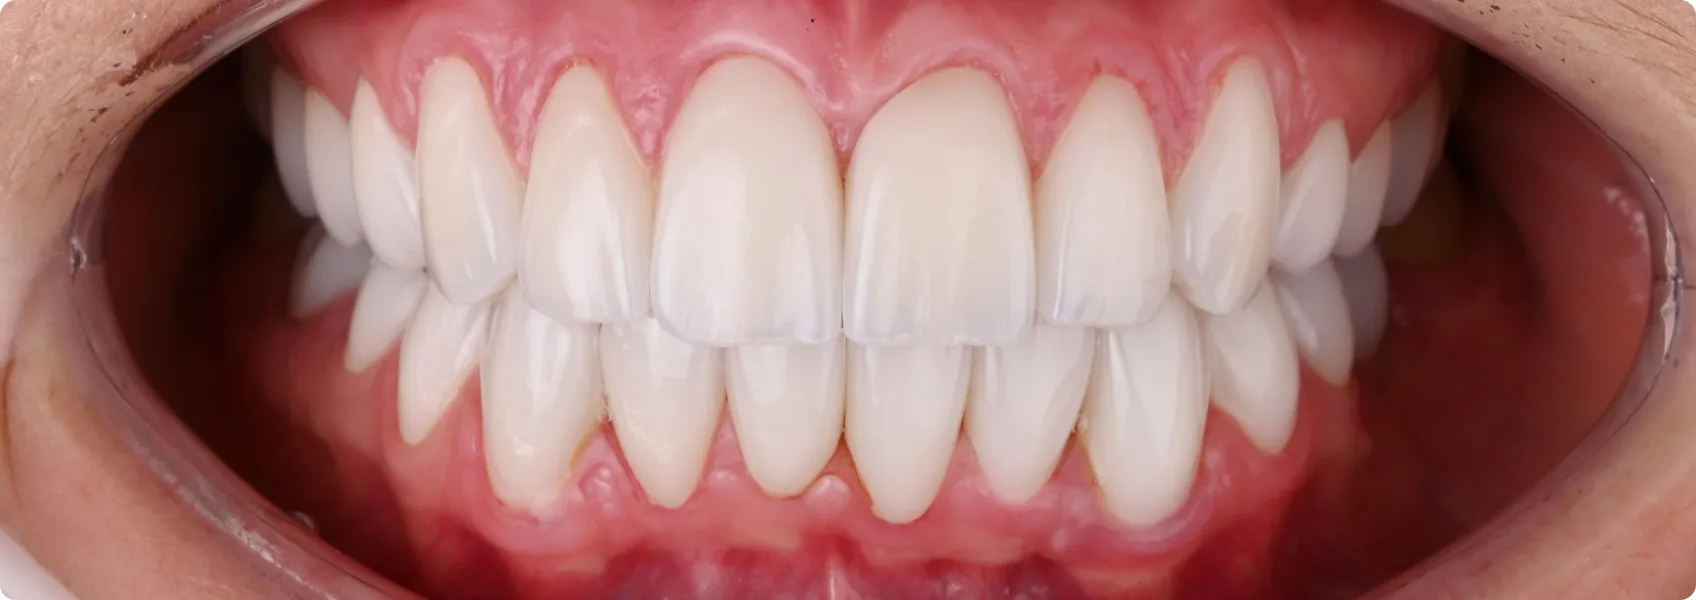

U Pacjentki fluoroza wystąpiła w obrębie zębów górnych oraz dolnych. Do NDC zgłosiła się po zakończonym leczeniu ortodontycznym w innej klinice.

Dr n. med. Ewa Chomik zaproponowała pełną rekonstrukcję funkcjonalno-estetyczną obu łuków za pomocą licówek.

Licówki to cienkie płatki porcelany, które przykleja się do przedniej strony oszlifowanego zęba. Zęby Pacjentki trzeba było jednak wybielić aż o 5 odcieni. Do tego wadliwa budowa szkliwa z fluorozą nie pozwalała na przyklejenie klasycznych licówek (adhezyjnych).

To oznaczało, że licówka musi być większa i grubsza, a oszlifowanie (preparacja) zęba — głębsze. Tylko w takim przypadku kolor będzie satysfakcjonujący, a licówka się nie odklei.

Wybór padł na licówki o poszerzonym zasięgu — tzw. korony częściowe.

To specjalny typ licówek, które pokrywają większą część zęba niż te klasyczne. Nie tylko przednią powierzchnię, ale również fragmenty powierzchni żujących, siecznych lub bocznych. Można je traktować jako „półkorony”, ponieważ łączą estetykę licówki z częściową funkcją ochronną korony protetycznej.

Efekt leczenia to nie przypadek. To wynik dziesiątek przemyślanych decyzji, precyzyjnej diagnostyki, współpracy lekarza z technikiem i ogromnego zaufania ze strony Pacjentki.

Od pierwszej konsultacji, przez planowanie cyfrowe, projektowanie uśmiechu, gingiwektomię, wax-up, mock-up, prowizorium i try-in — każdy etap miał znaczenie. Każdy był potrzebny, by rezultat był nie tylko piękny, ale też funkcjonalny i trwały przez lata.